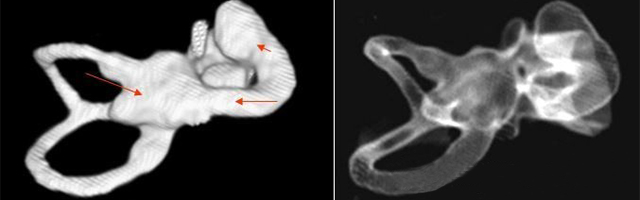

主要根據(jù)聽(tīng)力學(xué)表現(xiàn)和影像學(xué)檢查。通過(guò)高分辨CT可看到耳蝸畸形。內(nèi)耳MRI顯示膜迷路內(nèi)水充盈,耳蝸扁平,耳蝸第二圈與頂圈間隔缺損,以及半規(guī)管、前庭的畸形。

先天性耳蝸畸形伴前庭和外半規(guī)管發(fā)育不良